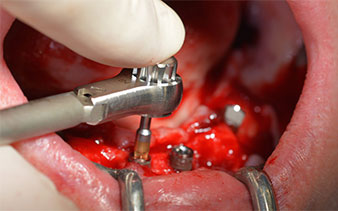

A continuación, se identificó el agujero mentoniano (foramen mentale) como la estructura anatómica límite y se alisó el cortical de la cresta ósea con la pieza de mano recta y una fresa redonda grande (fig. 4).

Este valor se corresponde con la posición siguiente del ajuste predefinido en Implantmed. Aquí se aprecia la inclinación de aproximadamente 45 grados del contra-ángulo de W&H hacia medio caudal en la región de la pieza 45 para preservar el nervus mentalis. El foramen mentale sirve como orientación anatómica para todas las perforaciones en esta zona. Las perforaciones siguientes se realizaron con una velocidad reducida de 300/rpm (figs. 10 y 11).